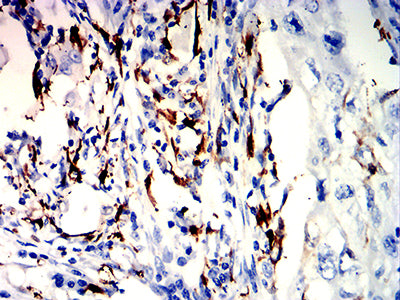

分类: 科研抗体货号: 32186别名: PTA1; DNAM1; DNAM-1; TLiSA1应用: IHC,FCM反应种属: Human

分类: 科研抗体货号: 32185别名: PTA1; DNAM1; DNAM-1; TLiSA1应用: IHC,FCM反应种属: Human

分类: 科研抗体货号: 32216别名: FRA应用: IHC,FCM反应种属: Human